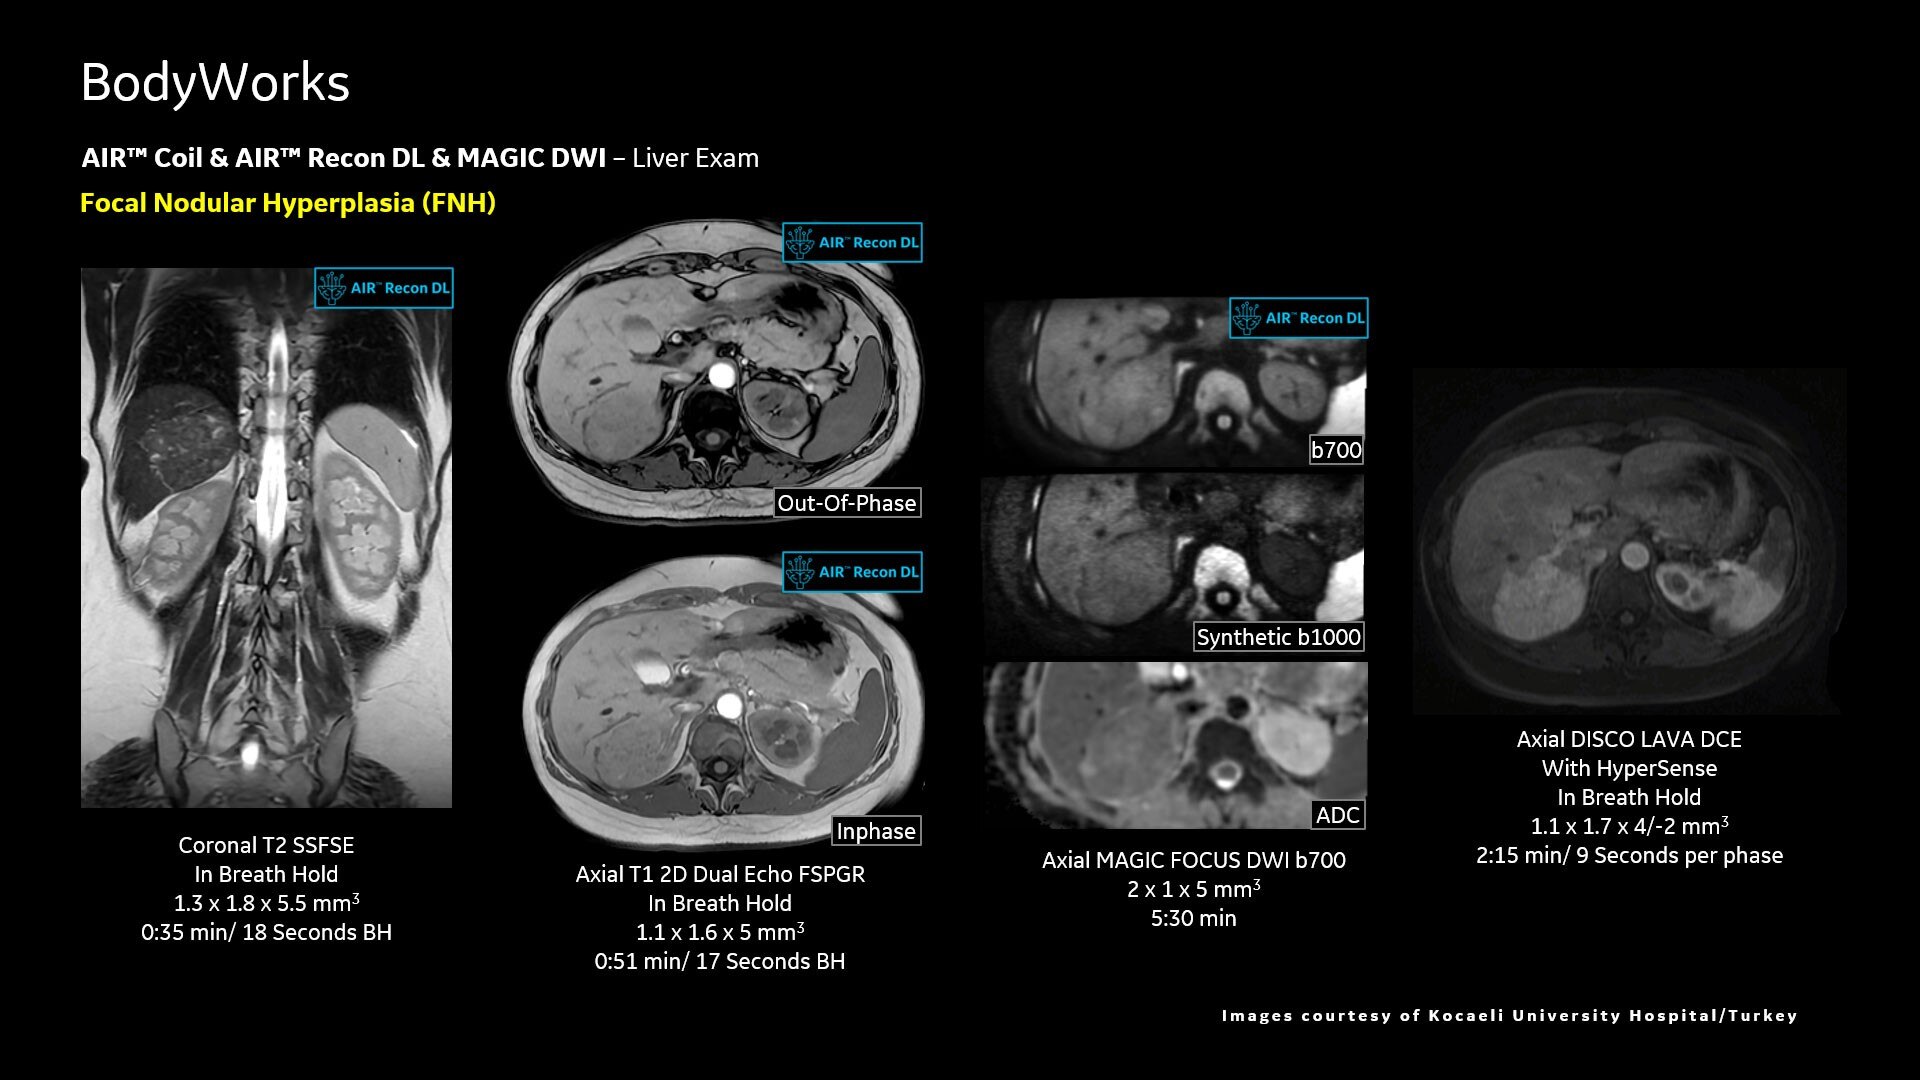

Adaptive AIR™ Coils accommodate all types of scans and patient sizes

AIR™ Recon DL improves SNR and image sharpness, enabling shorter scan times

Achieve a 25% efficiency gain with Ultra High Efficiency (UHE) gradient system. Fast, clear Total Digital Imaging (TDI) increases SNR by 25%. Improved IQ in 80% of cases without added time. Acquire higher SNR without a time penalty and get images virtually free of artifact with AIR™ Recon DL.***